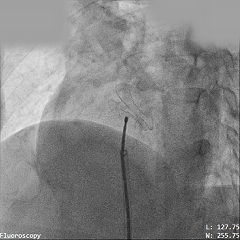

输送系统通过导丝送至左心房

将PannaWire多功能导丝作为加硬导丝,沿导丝加硬段送入输送鞘系统,导丝提供稳固支撑的同时减少加硬导丝器械交换,提高手术效率